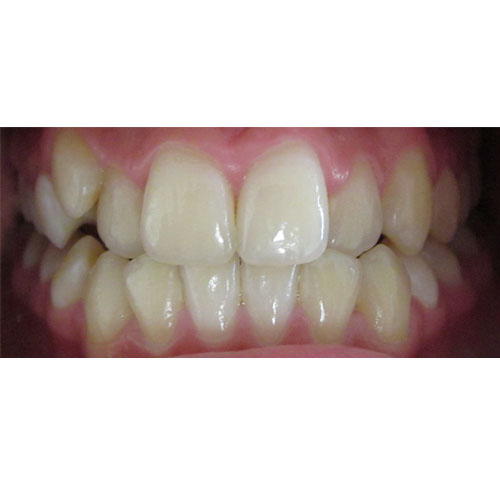

Nasze rezultaty